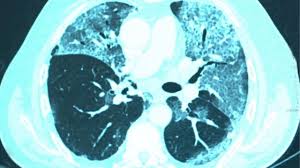

করোনায় ভালো হওয়ার পর ফুসফুসের জটিলতা

করোনাভাইরাসের সংক্রমণ-পরবর্তী অনেকের ফুসফুসে জটিলতা দেখা দিতে পারে। এই রোগকে বলা হয় পোস্ট কোভিড পালমোনারি ফাইব্রোসিস। এ রোগে ফুসফুসের নরম অংশগুলো শক্ত হয়ে ক্ষতের সৃষ্টি হয়। ফলে ফুসফুসের বায়ুকুঠুরিগুলো ঠিকমতো